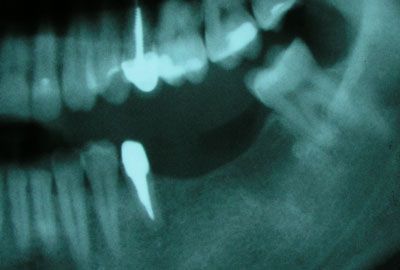

На прием к стоматологу-ортопеду пришел пациент с жалобой на отсутствие нижних коренных зубов и неудобство пережевывать пищу. При осмотре выяснилось, что отсутствующие нижние моляры (36 и 37 зубы - по международной классификации) удалены два года тому назад.

От протезирования с помощью мостовидной конструкции (в этом случае обтачиваются соседние здоровые зубы и на них ставятся опорные коронки) он отказался. Для выполнения надежной мостовидной конструкции нам пришлось бы обточить три зуба 34, 35 и 38, два из которых еще и депульпировать. С предложением установить два винтовых имплантата и последующем изготовлением металлокерамических коронок пациент согласился. Под местной анестезией была произведена установка двух винтовых имплантатов Astra Tech с одномоментной постановкой формирователей десны.